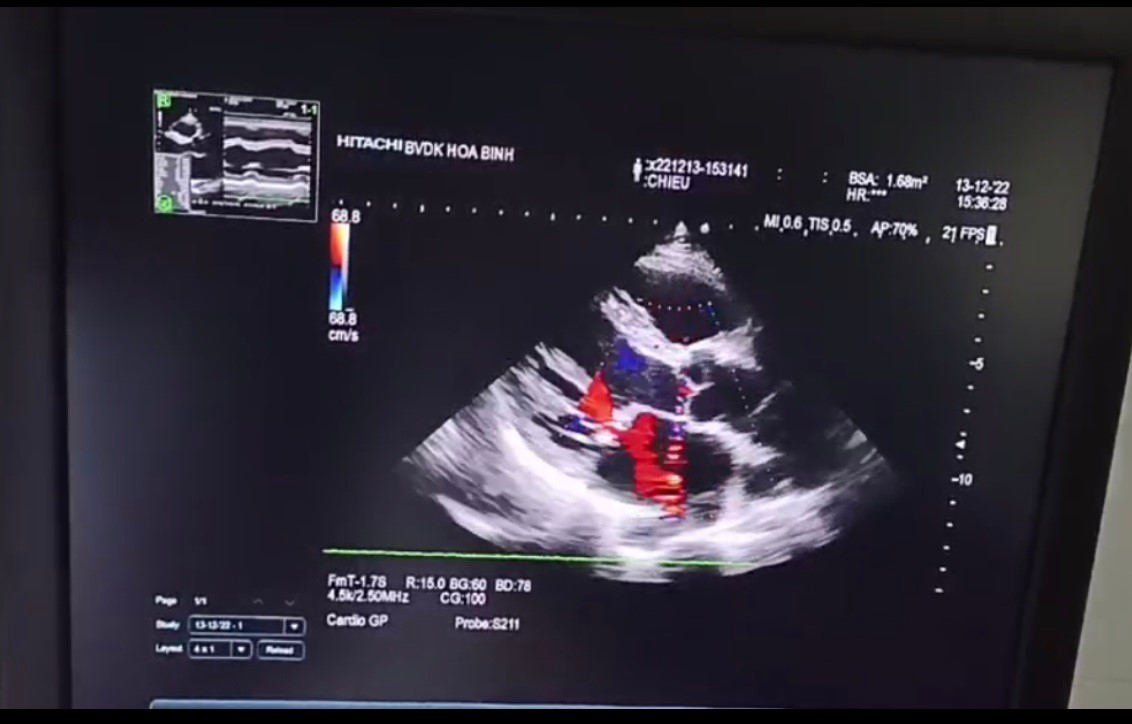

Hình ảnh siêu âm tim phát hiện bệnh nhân bị hẹp - hở van hai lá trong quá trình đi khám sức khoẻ định kỳ

Các chuyên gia Tim mạch, Bệnh viện Đa khoa tỉnh cho biết, van hai lá ngăn cách tâm nhĩ trái và tâm thất trái. Hẹp - hở van hai lá là tình trạng van không thể mở rộng trong thì tâm trương và đóng kín trong thì tâm thu như bình thường, gây ứ máu ở nhĩ trái. Lượng máu giàu oxy về tâm thất trái sẽ bị giảm sút, dẫn tới các mô và các cơ quan khác trong cơ thể không được nhận đủ oxy và các chất dinh dưỡng. Bệnh nếu không được phát hiện sớm sẽ rất nguy hiểm và có thể gây nhiều biến chứng ảnh hưởng đến sức khoẻ cũng như tính mạng người bệnh như suy tim, đột quỵ, rối loạn nhịp tim...